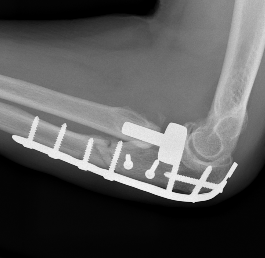

Olecranon plate + ORIF Type II coronoid process + radial head replacement

Olecranon plate with radial head replacement

Olecranon plate with radial head replacement + LCL repair

Olecranon plate + medial coronoid buttress plate + radial head replacement